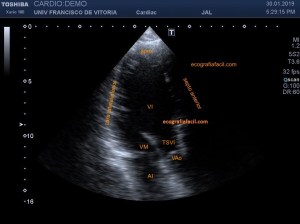

139. Ecocardiografía. Estudio Paraesternal Eje Largo.

141. Mediciones de los planos paraesternales.